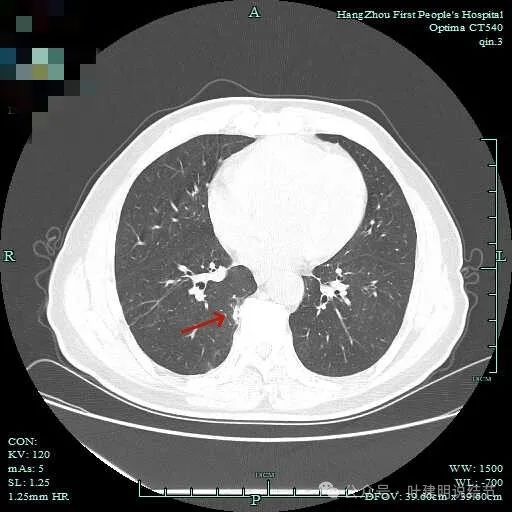

明显胸膜牵拉以及血管进入,灶内密度不纯。

边缘毛糙有细毛刺,灶内密度不均;胸膜牵拉以及表面不平;黄色箭头示细支气管截断的样子。

血管征以及胸膜凹陷征。

轮廓与边界清,灶内有小空泡征。

多支血管进入,灶内密度不均。

胸膜牵拉,表面不平,血管进入并有异常增粗。